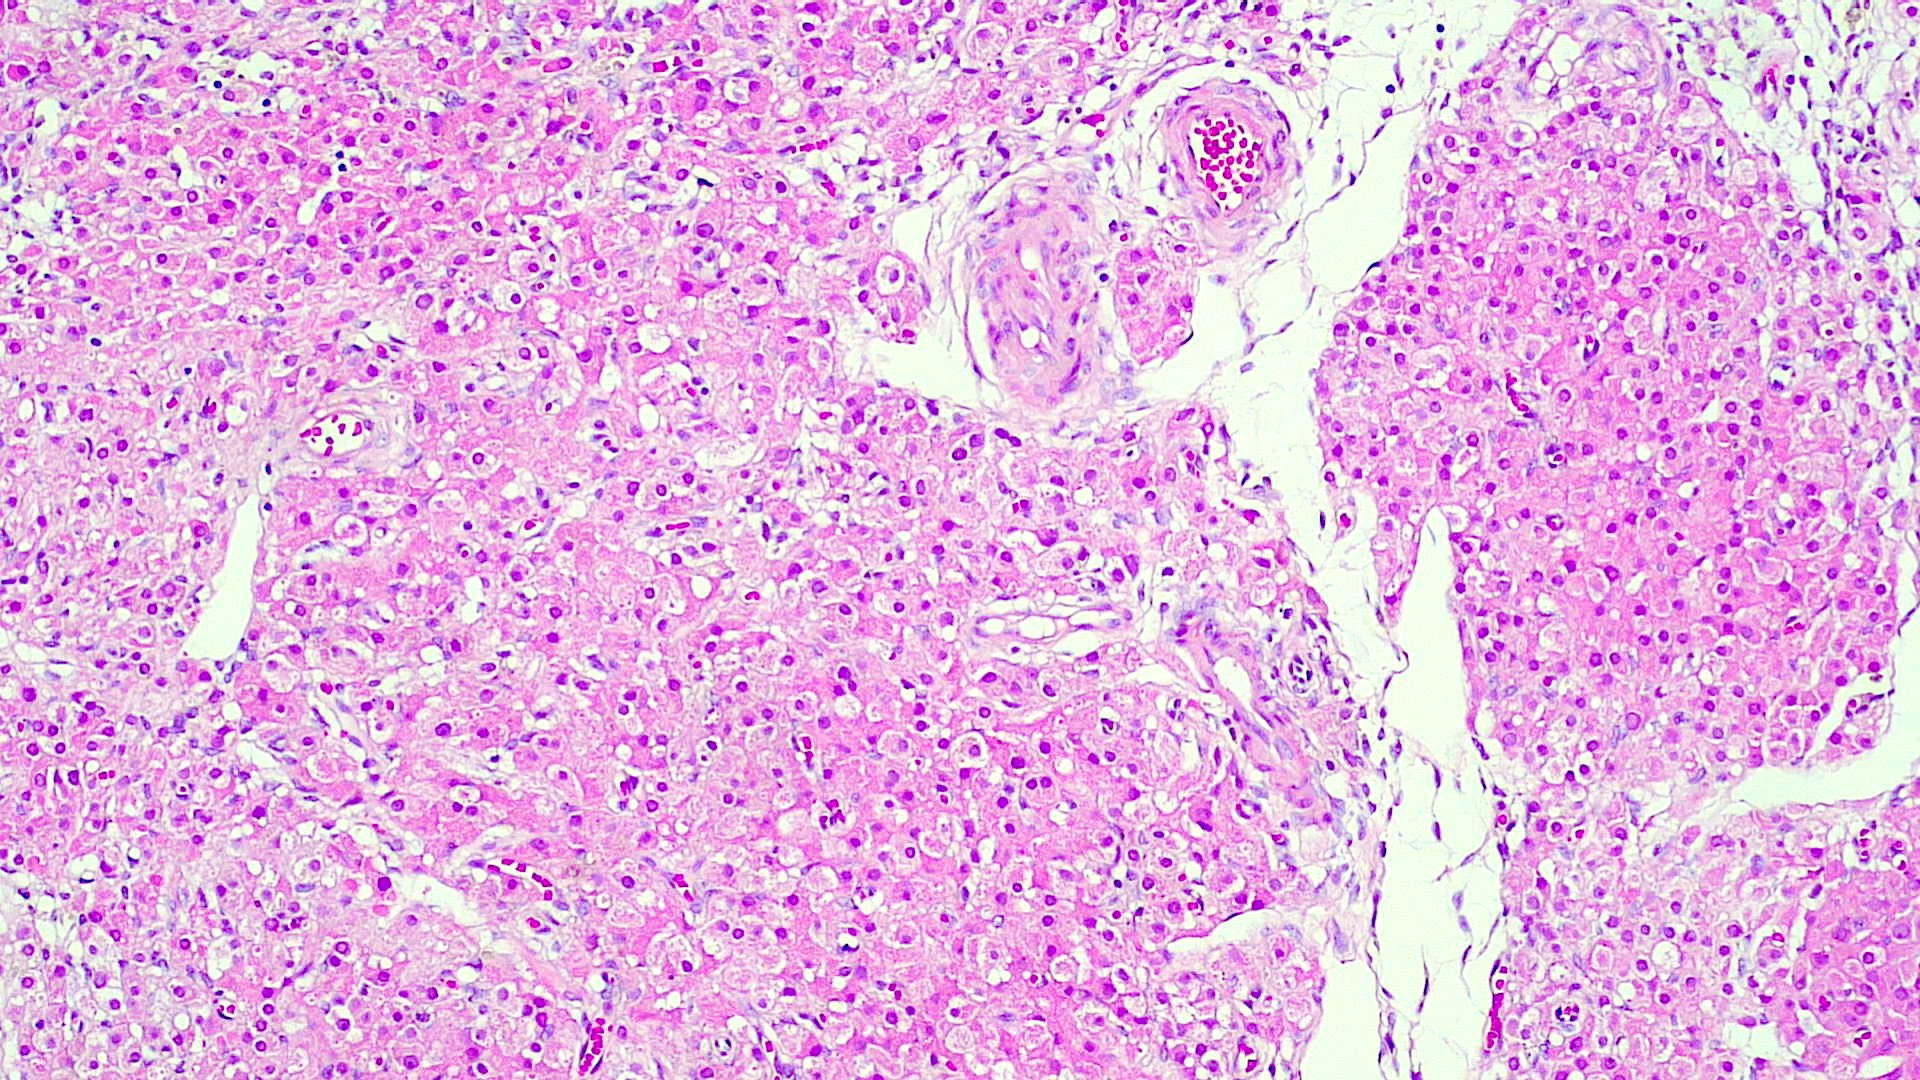

Vulvar skin biopsy. Erythematous pruritic eruption. Your diagnosis?

Only H&E stain needed for this one!